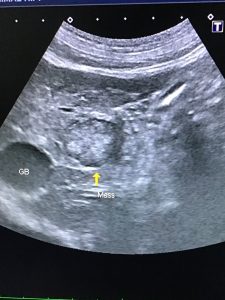

10歳の柴犬が毎年行っているフィラリア検査と一緒に健康診断を兼ねた血液検査を実施した。昨年までは全く異常がなかったが今回はALTとASTという2つの肝酵素が高値だったため、念のためX線検査と超音波検査を実施した。X線検査で腹腔内に針のような細い金属らしきものが認められたが、飼い主様は心当たりがないとのことだった。また超音波検査では肝臓の外側左葉に約2㎝ほどの低エコー部と、右葉に複数の1㎝台の低エコー部が認められた。次に針状異物が管腔臓器内か外なのかの区別と肝臓のマス病変の確認のため、検査センターにてCT検査を行なった。その結果、針状異物は管腔臓器の外側に存在していることが判明。また造影剤投与後のCT検査で約2.4㎝の腫瘍らしいものが1ヶ所と複数の嚢胞と思われるものが確認された。その後肝臓外側左葉にある2.4㎝の腫瘤の切除と針状異物の摘出手術を実施した。肝臓の摘出腫瘤は病理組織検査で肝細胞癌だった。マージンの血管内浸潤はマイナスだったので、とりあえず一安心だが、定期的な検査は必要だ。肝細胞癌は遠隔転移はほとんどないが、肝臓内に再発することはあり得るため、経過を見ながら定期検査をすることが大切だ。いずれにしても、今回はフィラリアの検査と一緒に健康診断をすることで、針状の異物と肝臓の腫瘍が発見でき、さらにこの針状異物と肝細胞癌を摘出することが出来たため、健康診断の有用性が改めて確認できた。